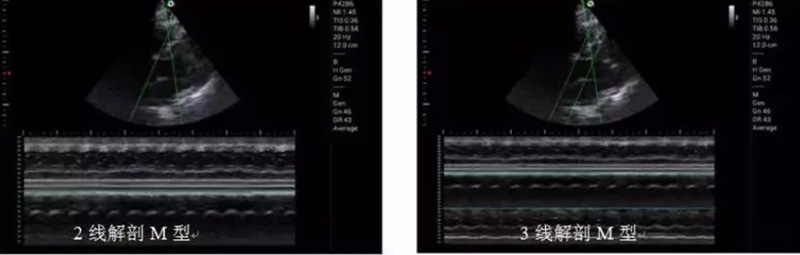

心臟應用方面,M20解剖M型模塊M型取樣線可360度任意旋轉,可同時選取3條M型取樣線,在方便快捷的進行心功能評估時,可以從不同階段不同瓣口評估心肌運動。